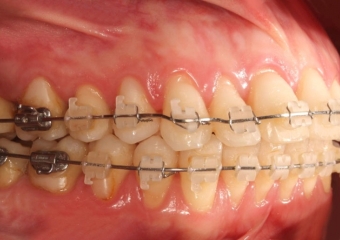

Mordida inicial